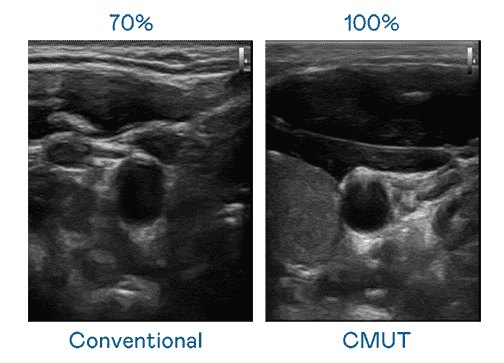

CMUT 技术是一种用电容式微机电元件来产生超音波讯号的技术。。与传统 PZT 压电式技术相比,,CMUT 频宽增加 30%,,,更宽频的超音波讯号让影像解析度大幅提升,,,,是实现高影像品质医疗超音波扫描、、、促进精准医疗发展的关键技术。。。

大频宽带来超清晰影像

超音波影像的解析度高低,,,,首先取决于探头能发出的讯号频宽。。888.BY集团电子游戏 CMUT 可提供高清晰的超音波讯号,,,提供高频宽、、高灵敏度、、影像纹理细节更高的超音波影像,,协助医护人员缩短影像判读时间及利用精准的医疗影像进行诊断。。。